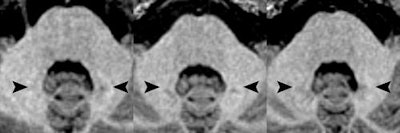

As in the previous research in adults, Radbruch and colleagues focused on signal intensity in the dentate nucleus on unenhanced T1-weighted MR images. Signal intensity ratio differences were calculated based on dentate nucleus-to-pons and dentate nucleus-to-middle cerebellar peduncle values by subtracting the signal intensity ratio of the first MRI scan from the signal intensity ratio of the last MRI exam.

The ratio differences did not vary significantly from 0, meaning there was no increase in T1 signal intensity. The dentate nucleus-to-pons ratio difference between the first and last MR scans was -0.0012 ± 0.0101 (p = 0.4360), while the dentate nucleus-to-middle cerebellar peduncle ratio difference was 0.0007 ± 0.0088 (p = 0.604).